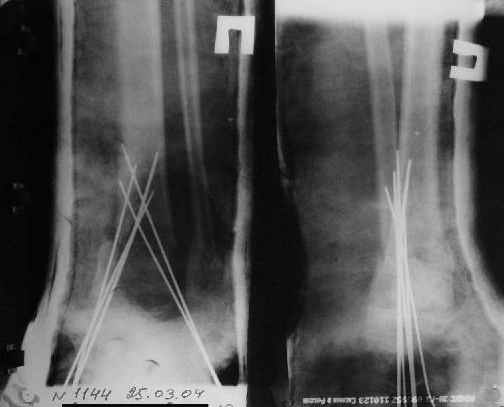

Так как речь зашла непосредственно о травме, см этапные

снимки. Как все было

Первичные

Вытяжение